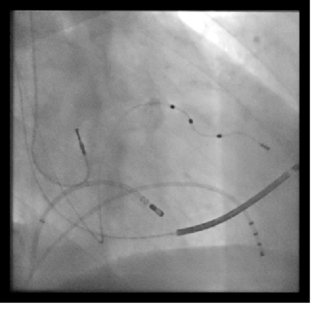

Previa anestesia locale in sede femorale, si procede tramite tecnica di Seldinger, ad incannulamento della vena femorale destra. Attraverso questo accesso venoso si fa avanzare un catetere ablatore in prossimità del nodo atrio ventricolare (parte compatta). Erogando radiofrequenza, si interrompe la comunicazione elettrica tra atri e ventricoli permettendo così al dispositivo impiantato di stimolare il cuore alla frequenza desiderata.